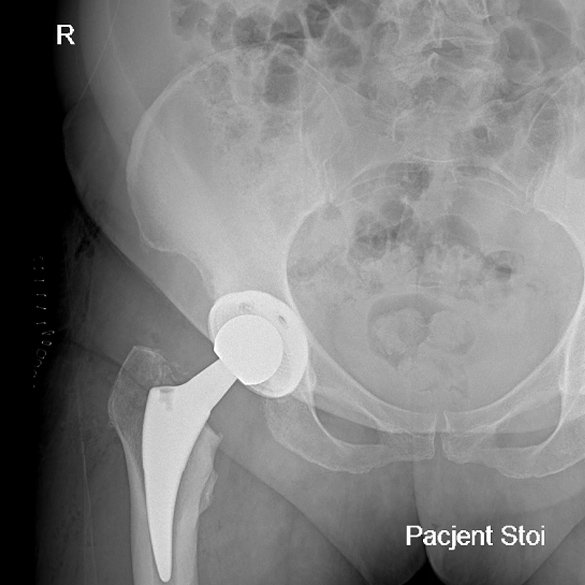

Endoproteza stawu biodrowego

Endoprotezoplastyka stawu biodrowego to skuteczna metoda leczenia choroby zwyrodnieniowej, jałowej martwicy głowy kości udowej, dysplazji oraz innych zmian zwyrodnieniowo-destrukcyjnych stawu jak i złamań szyjki kości udowej. Zabieg polega na usunięciu zniszczonych struktur stawu i zastąpieniu ich odpowiednio dobranym implantem, przywracającym funkcję, ruchomość i komfort życia.